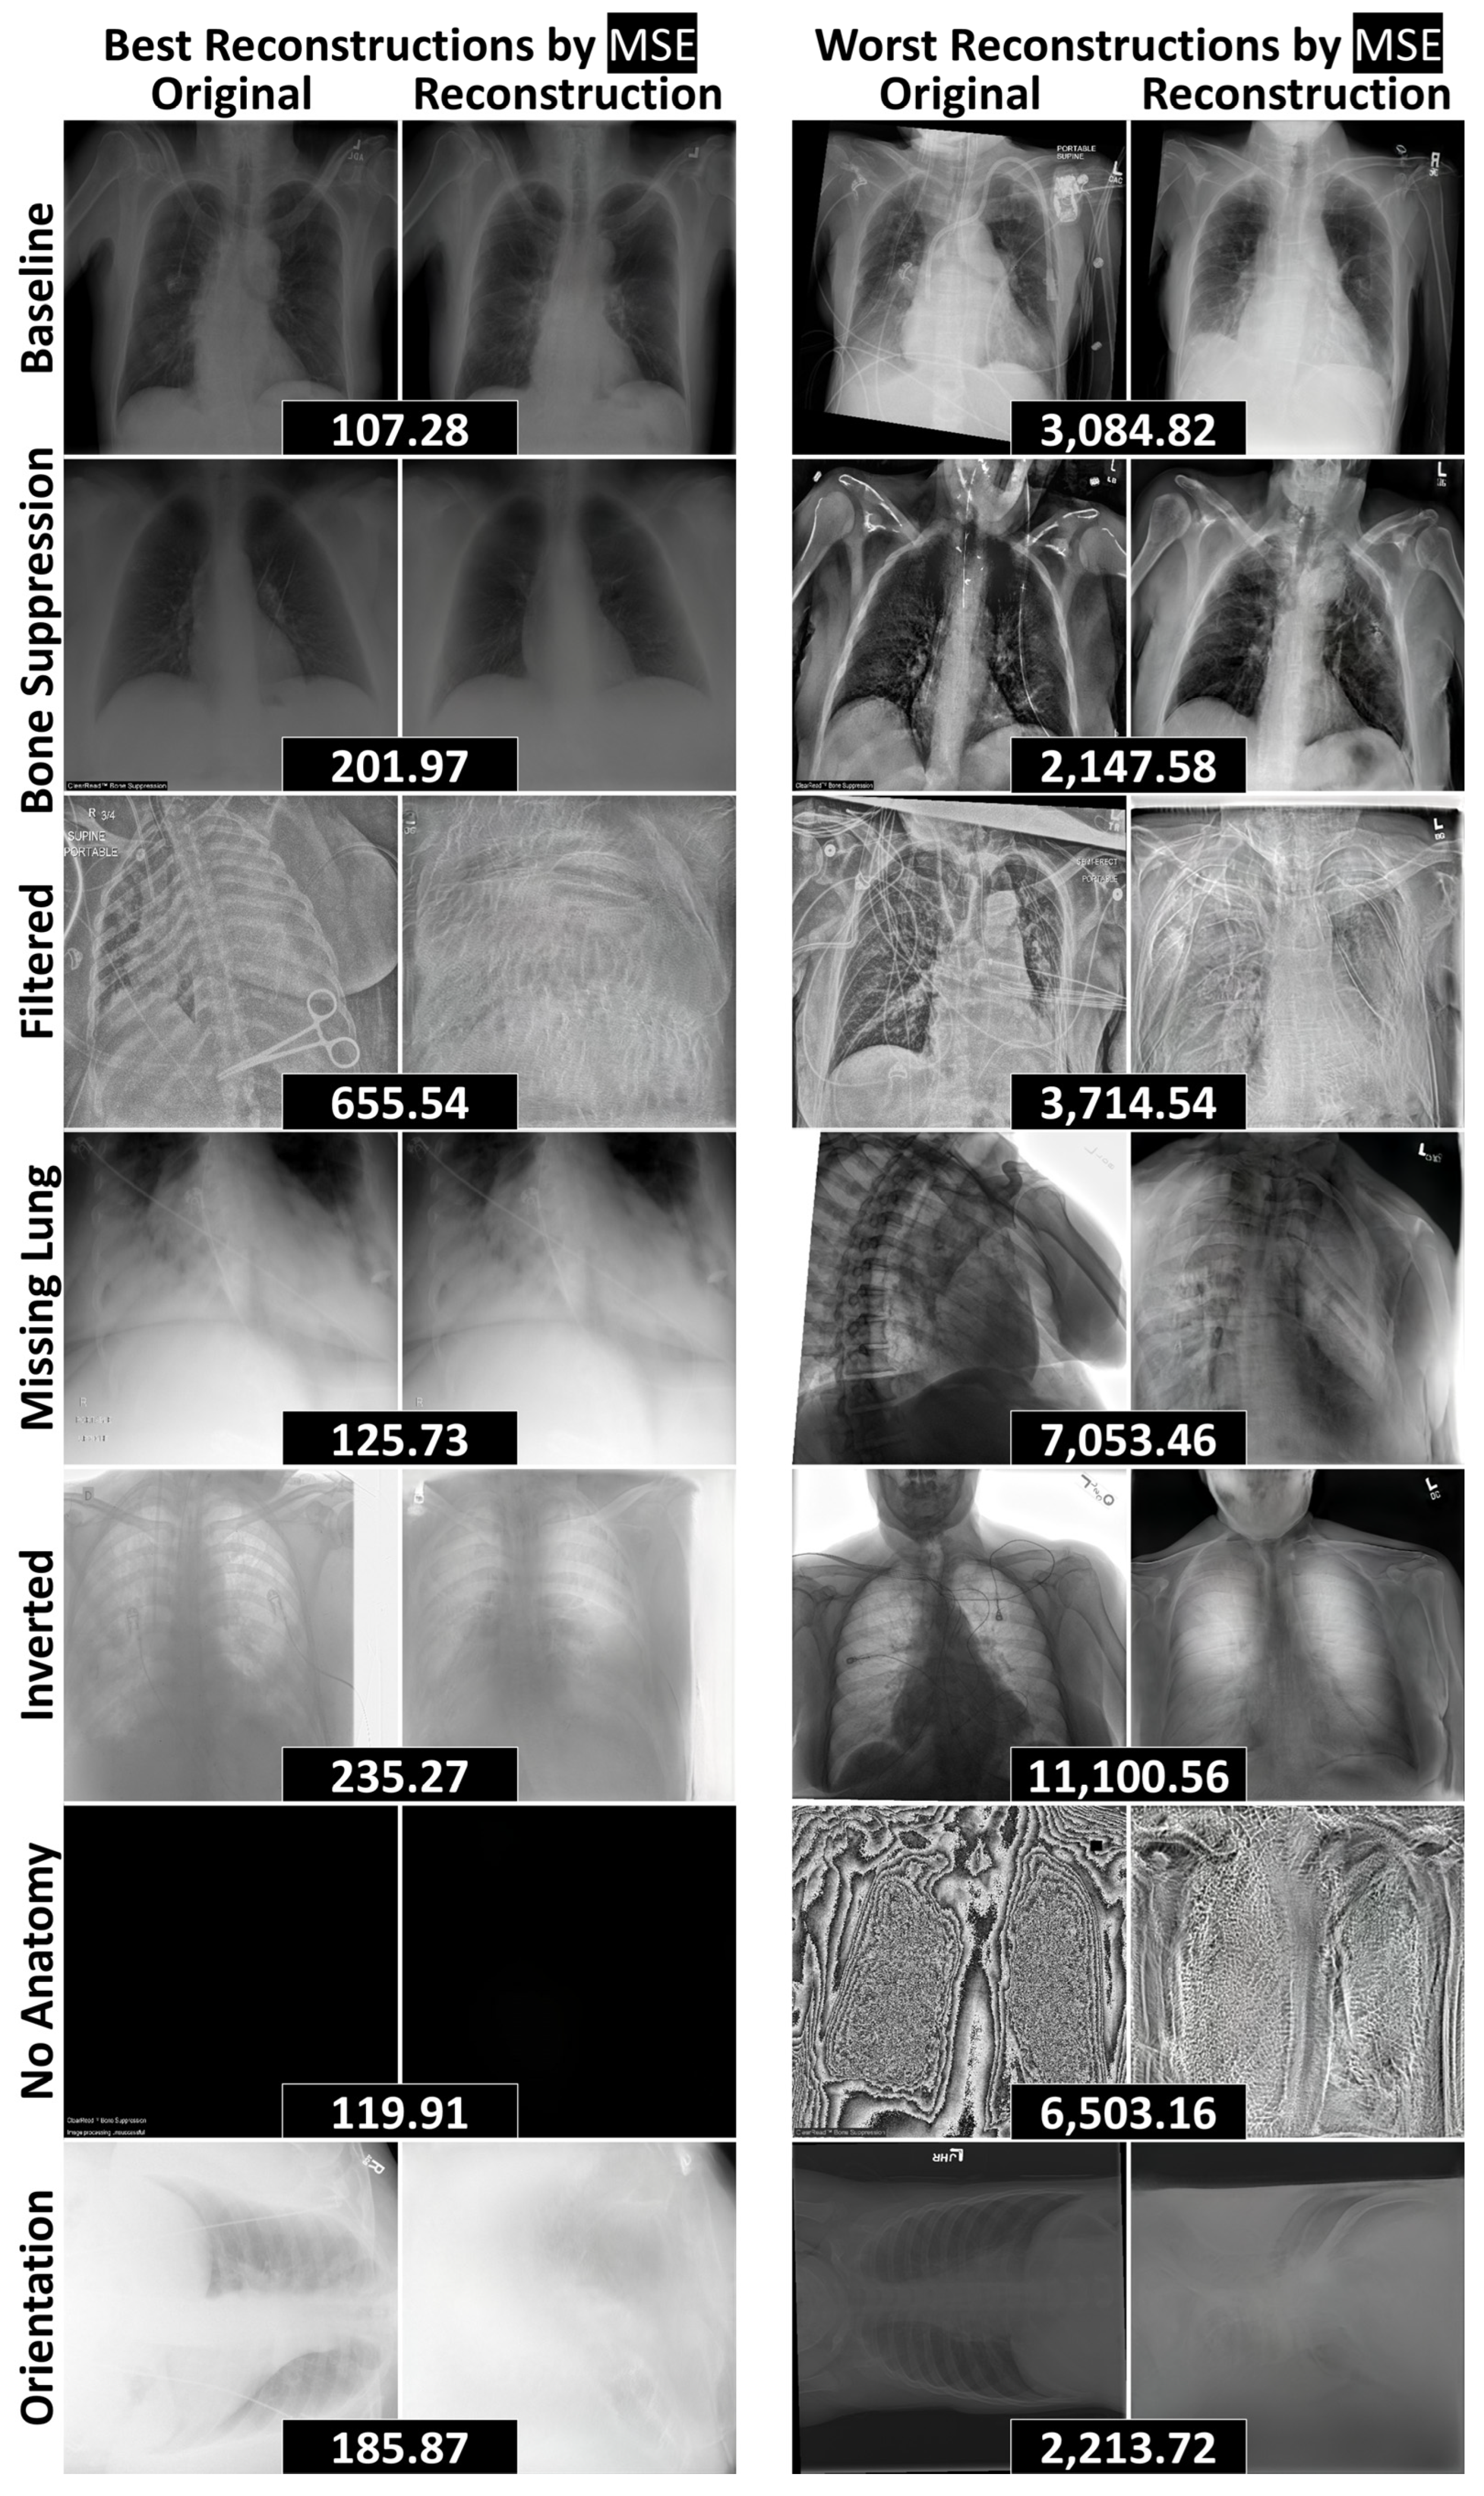

3.2. Reconstruction Performance and Interpretation

3.3. Quantitative Anomaly Detection Performance